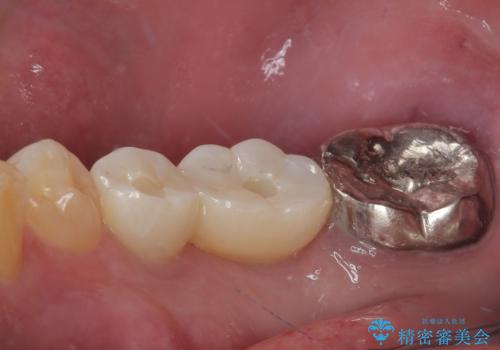

抜歯即時埋入部と後方の欠損部は、即日荷重(インプラント埋入と同時に仮歯を装着すること)が可能な安定値が得られましたが、長い期間欠損した状態で過ごすと、欠損部に舌を押し当てる癖が発現してしまい、舌からの側方圧でインプラントが脱離するリスクが著しく高まってしまうため、即日荷重は行いませんでした。

おかげでインプラントは無事に生着し、僅か4ヶ月で治療を終えることができました。